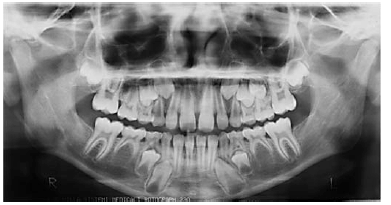

Tendo como base a imagem apresentada, que reproduz uma radiografia panorâmica e os conhecimentos odontológicos correlatos, julgue os itens a seguir.